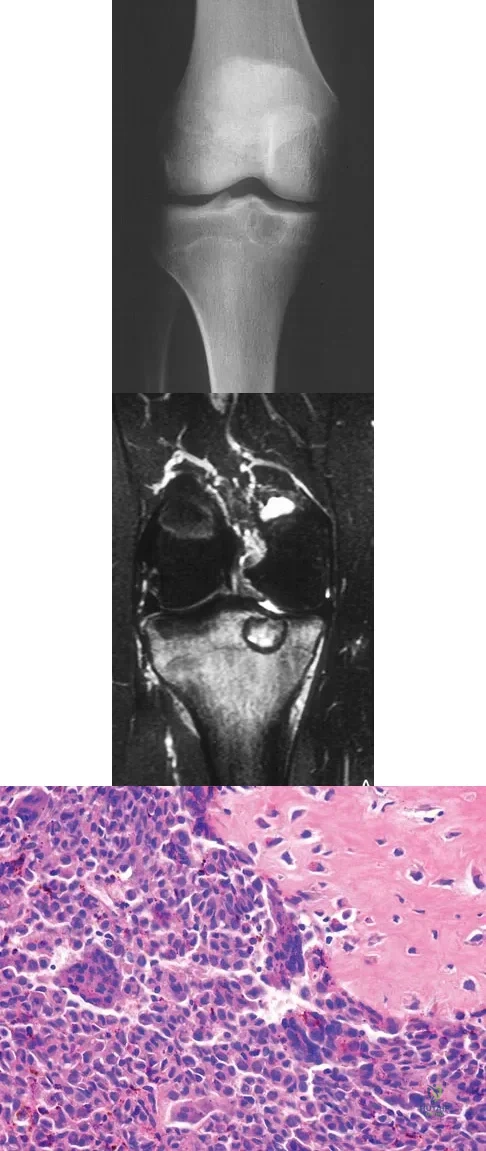

A 15-year-old girl reports a 6-month history of activity-related knee pain and swelling. A radiograph, MRI scan, and biopsy specimen are shown in Figures 21a through 21c. What is the most likely diagnosis?

Explanation

Figures 19a and 19b show the AP and lateral radiographs of an 18-year-old man who has had knee pain for 3 months. Figure 19c shows a histopathologic photomicrograph of the biopsy specimen. Which of the following factors is most likely to affect his survival?

Explanation